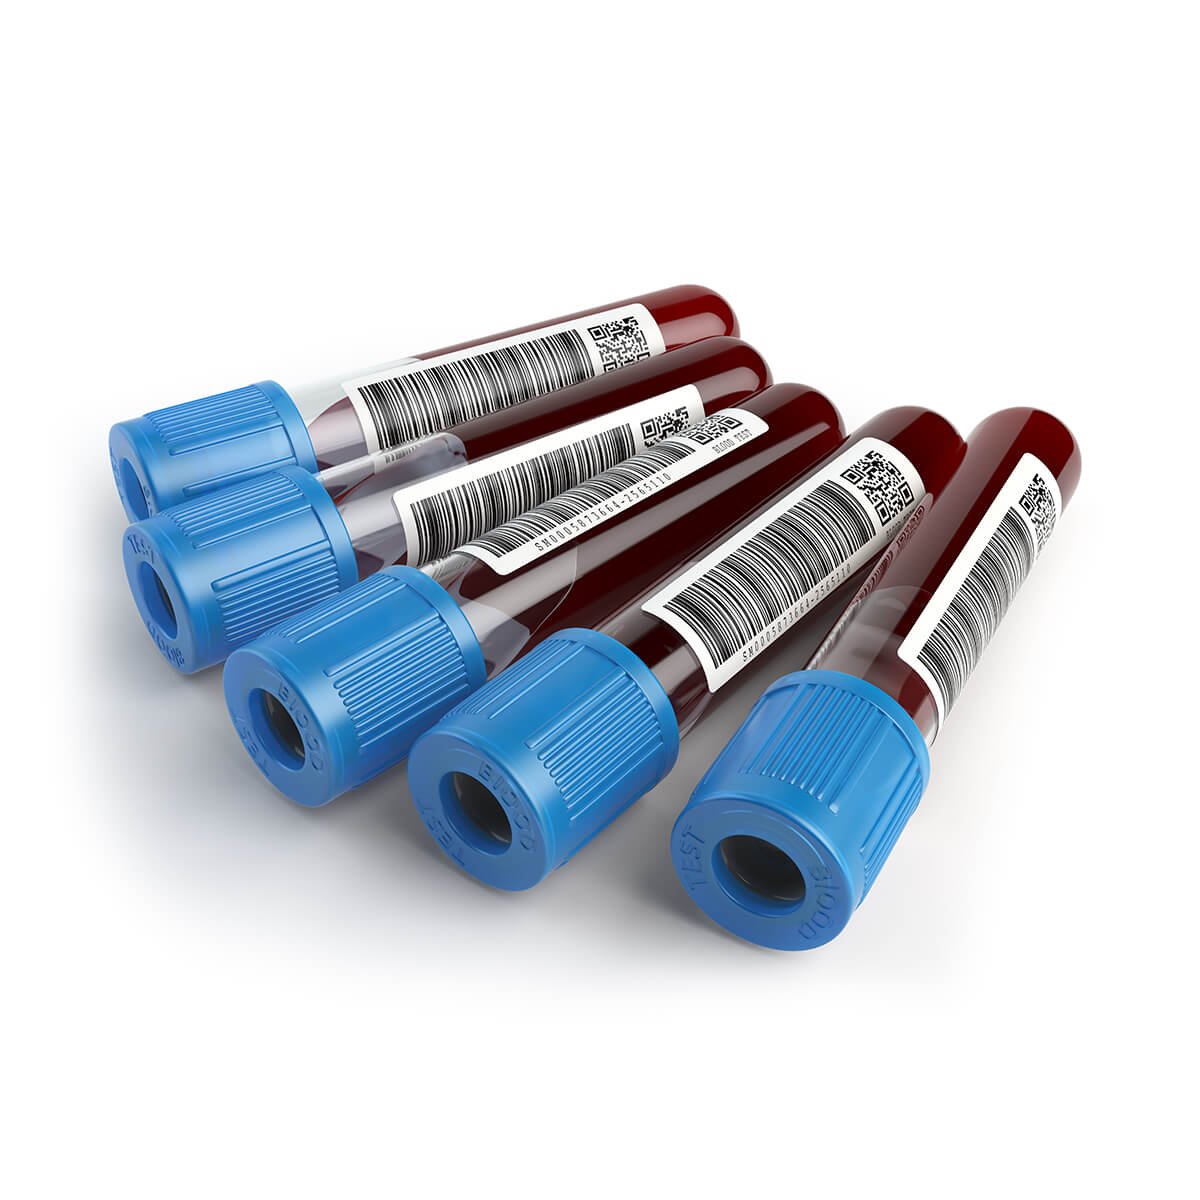

Small medical box

Original price was: £18.00.£16.00Current price is: £16.00.Sold out